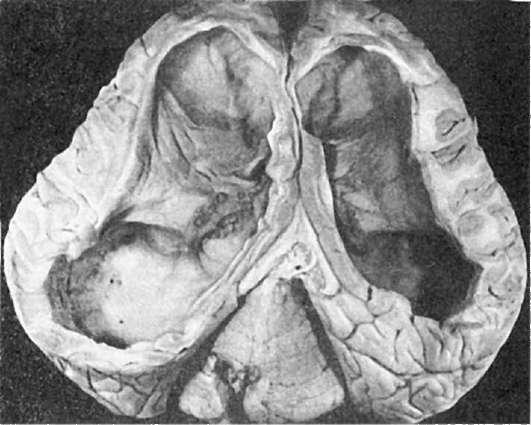

Врожденная гидроцефалия - избыточное накопление ликвора в желудочках мозга (внутренняя гидроцефалия)или в субарахноидальных пространствах (наружная

гидроцефалия) (рис. 294) сопровождается увеличением мозгового черепа и резким несоответствием его с лицевым - лицо кажется маленьким, лоб - нависшим. Наблюдаются расхождение и ис-

Рис.

294. Гидроцефалия (по А.В. Цинзерлингу)

тончение костей черепа, выбухание родничков. Нарастает атрофия вещества головного мозга, в большинстве случаев связанная с нарушениями оттока ликвора вследствие стеноза, раздвоения или атрезии водопровода большого мозга (сильвиева водопровода), атрезии срединных и боковых отверстий IV желудочка и межжелудочкового отверстия.